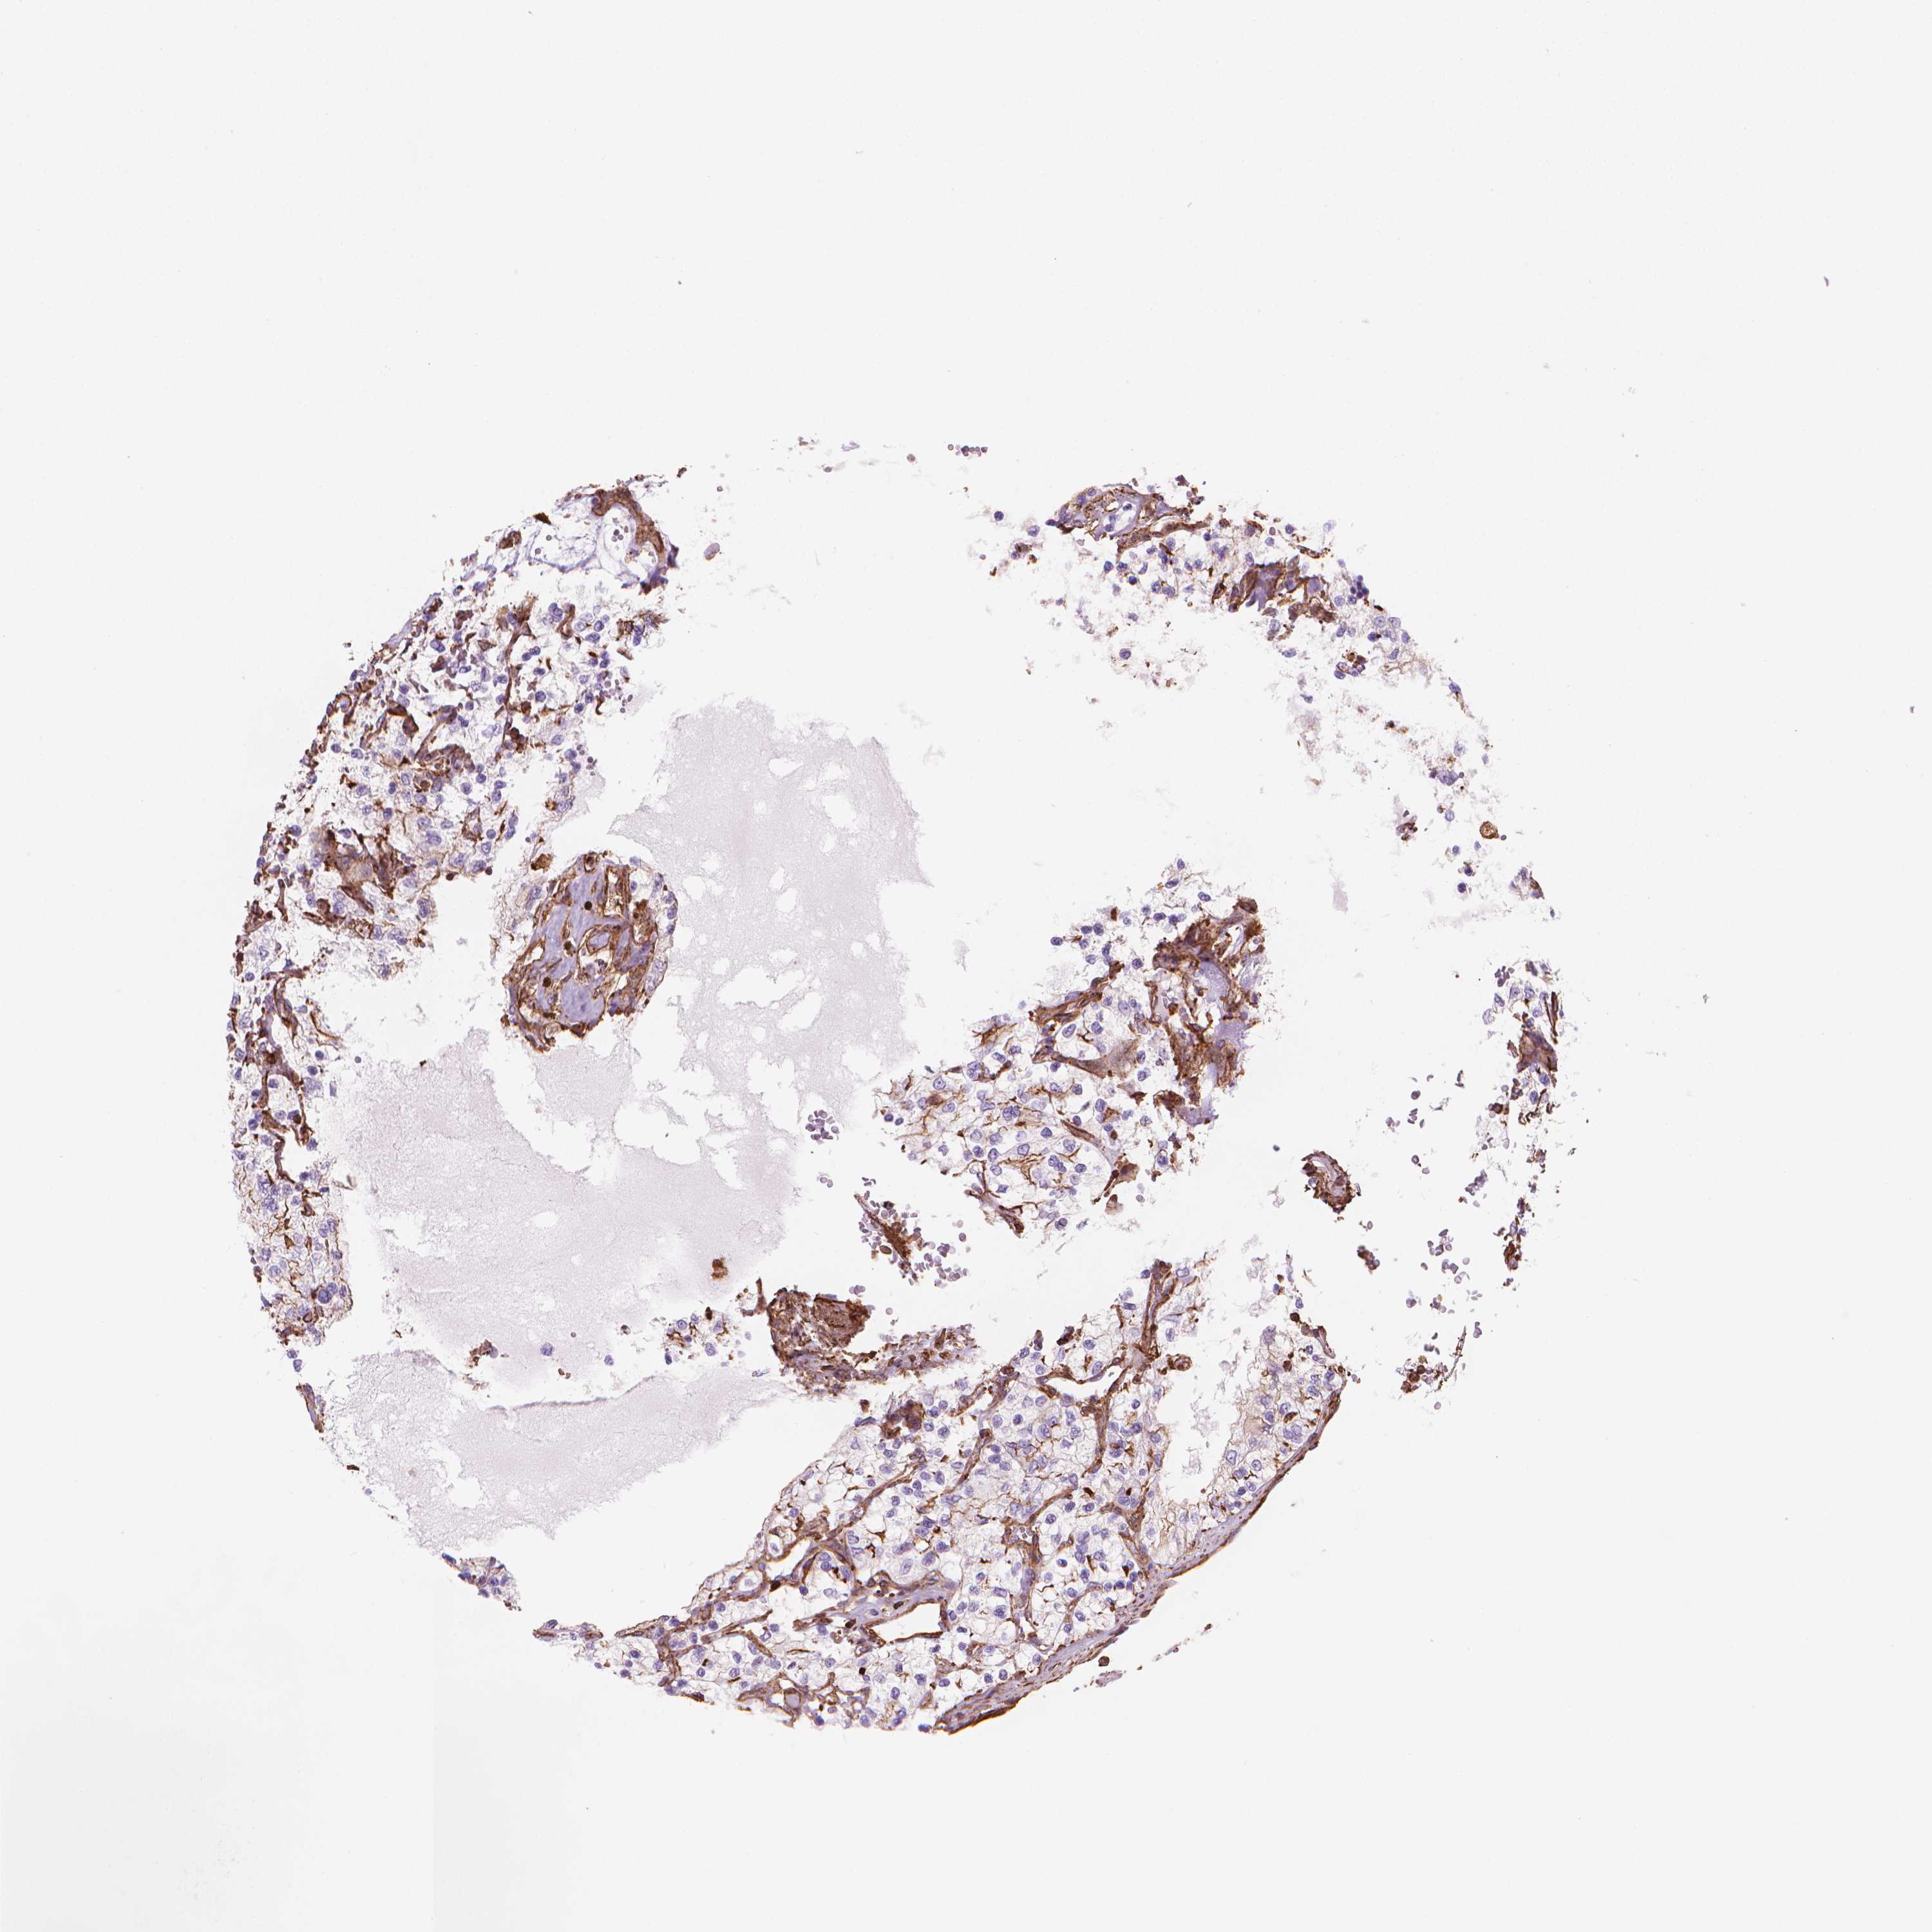

KIDNEY RENAL PAPILLARY CELL CARCINOMA (TCGA) - Interactive survival scatter ploti

The Survival Scatter plot shows the clinical status (i.e. dead or alive) for all individuals in the patient cohort, based on the same data that underlies the corresponding Kaplan-Meier plots. Patients that are alive at last time for follow-up are shown in blue and patients who have died during the study are shown in red.

The x-axis shows the expression levels (FPKM) of the investigated gene in the tumor tissue at the time of diagnosis. The y-axis shows the follow-up time after diagnosis (years). Both axes are complimented with kernel density curves demonstrating the data density over the axes. The top density plot shows the expression levels (FPKM) distribution among dead (red) and alive patients (blue). The right density plot shows the data density of the survived years of dead patients with high and low expression levels respectively, stratified using the cutoff indicated by the vertical dashed line through the Survival Scatter plot. This cutoff is automatically defined based on the FPKM cutoff that minimizes the p-score. The cutoff can be changed by dragging the vertical line or by entering a cutoff value in the square labeled "Current cut-off".

Under the Survival Scatter plot the p-score landscape (black curve; left axis) is shown together with dead median separation (red curve; right axis). Dead median separation is the difference in median mRNA expression between patients who have died with high and low expression, respectively. It is calculated as follows: median FPKM expression of dead patients with high expression - median FPKM expression of dead patients with low expression. This is intended to aid the user in visually exploring custom cutoffs and the associated p-scores and dead median separation.

Individual patient data is displayed and can be filtered by clicking on one or more of the category buttons on the top of the page. Categories describing expression level and patient information include: high, low, alive, dead, female, male and tumor stages. The scale of the x-axis can be toggled between linear and log-scale by clicking on the "x log" button. Mouse-over function shows TCGA ID, patient information and mRNA expression (FPKM) for each patient.

& Survival analysisi

Kaplan-Meier plots summarize results from analysis of correlation between mRNA expression level and patient survival. Patients were divided based on level of expression into one of the two groups "low" (under cut off) or "high" (over cut off). X-axis shows time for survival (years) and y-axis shows the probability of survival, where 1.0 corresponds to 100 percent.

PATJ is not prognostic in Kidney Renal Papillary Cell Carcinoma (TCGA)

Best expression cut offi

Based on the FPKM value of each gene, patients were classified into two groups and association between prognosis (survival) and gene expression (FPKM) was examined. The best expression cut-off refers the FPKM value that yields maximal difference with regard to survival between the two groups at the lowest log-rank P-value. Best expression cut-off was selected based on survival analysis .

When clicking on this number, the vertical dashed line indicating cut-off, the interactive survival plot, and the Kaplan-Meier curve will be adjusted to show results based on the best expression cut-off.

: 36.33